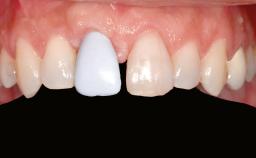

Shell Technique for Horizontal and Vertical Maxillary Bone Augmentation in a Partially Edentulous Patient with Aggressive Periodontal Disease

Prosthesis Type FDP

Patient's Esthetic Expectations Low Medium High

Lip Line No exposure of papillae Exposure of papillae Full exposure of mucosa margin

Periodontal Phenotype Low-scalloped, thick Medium-scalloped, medium-thick High-scalloped, thin